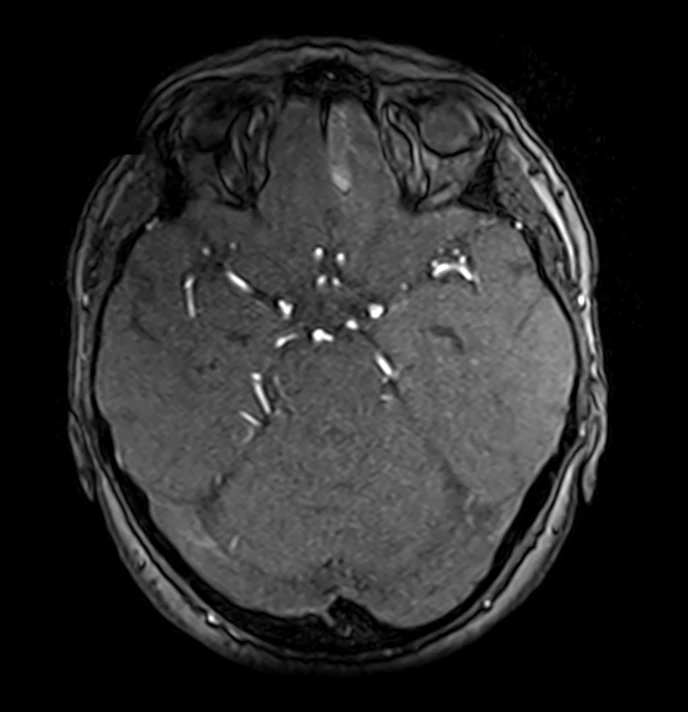

Семь менингиом и метастаз (рака молочной железы).

Четко видно, как по строению отличаются доброкачественные опухоли от злокачественных.

Первые яркие, четкие, шаровидные/полушаровидные, видно прикрепление широким основанием к костям, даже у самой мелкой.

А метастаз неровный, неяркий, нечеткий, неровный, из-за некроза, инвазии в мозг и перифокального отека.

Смотрим и запоминаем!